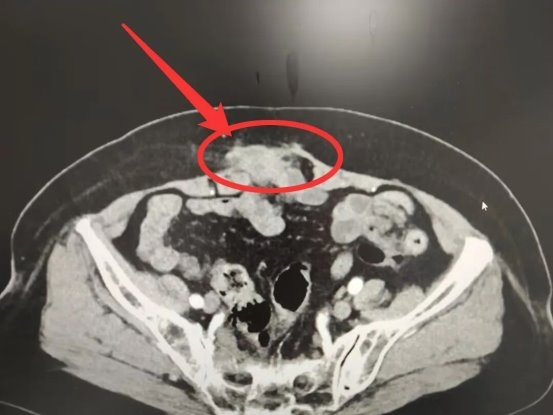

入院后,普外科陈庆城副主任医师进行了详细检查:站立时腹部切口处可见约5cm*9cm的肿物,平卧后探查发现局部腹壁内层缺损约3cm*5cm。